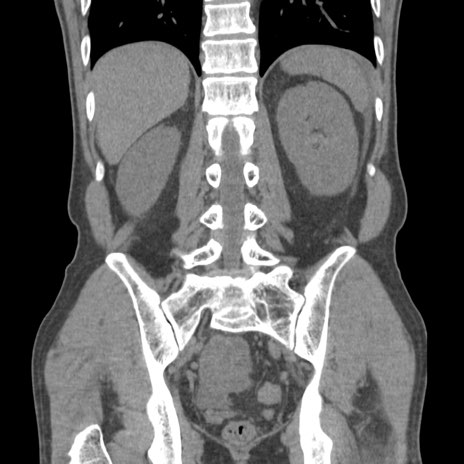

症例56 CT(冠状断像)

横断像